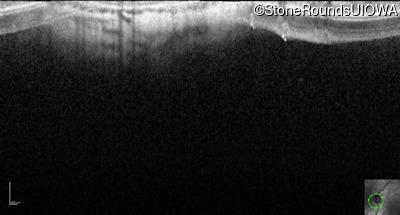

Optical Coherence Tomography - Right - 10/160 sc

Exemplar

Optical Coherence Tomography - Left - 10/200 sc

Exemplar / OCT Stack